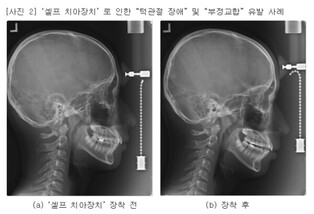

치협 “검증되지 않은 셀프 치아 장치, 오히려 구강 건강 해쳐”